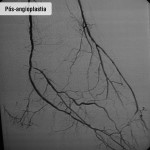

Angioplasita renal

O que é

Técnica cirúrgica minimamente invasiva indicada, basicamente, para casos de estenoses críticas (acima de 70%) de uma ou de ambas as artérias renais com comprometimento da função dos rins.

Como funciona

Todo o procedimento é realizado “por dentro dos vasos sanguíneos”, através de uma punção na região da virilha. Não há cortes ou necessidade de pontos. Uma anestesia local é empregada junto com uma sedação leve.

São introduzidos cateteres até o vaso acometido através do qual é implantado um stent (tubo metálico que mantém o vaso aberto), que é expandido por um balão. A taxa de sucesso do procedimento é de 95%, ou seja, em apenas 5% das vezes não é possível implantar o stent.

Pós-operatório

Os cuidados consistem em hidratação e monitoração da função renal. O paciente é liberado para andar já no dia seguinte. Em vista da natureza pouco agressiva do procedimento, o retorno às atividades habituais e mesmo ao trabalho, ocorre entre 1 a 2 dias.

Fotos